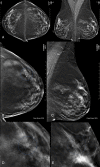

Materials and methods: A deep learning AI system was developed to identify suspicious soft-tissue and calcified lesions in DBT images. A reader study compared the performance of 24 radiologists (13 of whom were breast subspecialists) reading 260 DBT examinations (including 65 cancer cases) both with and without AI. Readings occurred in two sessions separated by at least 4 weeks. Area under the receiver operating characteristic curve (AUC), reading time, sensitivity, specificity, and recall rate were evaluated with statistical methods for multireader, multicase studies.